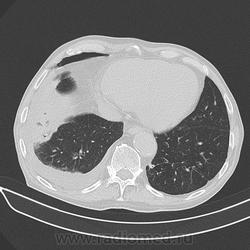

Мужчина 72 лет, лежит в кардиологии с ИБС.

Температуры нет, ОАК - Le - 10, сдвига формулы нет;  кашель редкий не продуктивный, иногда С ПРОЖИЛКАМИ КРОВИ.  Слабость, одышка.

Дренировали. получили 1,5 л серозно-геморрагической жидкости.

Спустя несколько дней провели КТ  "для исключения онко-патологии".

p.s.  обратите внимание на зону аналогичного уплотнения в левом легком (видно на аксиалах).

Дайкомов не вижу, по джипегам расценил бы как ТЭЛА с субсегментарными инфарктами легких, достаточно характерная, как-бы "всепененная" структура.

,.. и гидротораксом справа, и (осумкованным/ограниченным-?) пневмотораксом (в переднем отделе, параперикардиально, опять же, справа)... Или пневмоперитонеум туда добрался... по неисповедимым своим путям?

я думаю пневмоторакс может быть последствием "криво" выполненной плевральной пункции.

Вы думаете, что пневмоторакс? Может быть уже брюшная полость.

Уверен. Посмотрите пятый по счету коронал, в области верхушки. Немного свободного воздуха в плевральной полости есть. И это не опровергает наличие воздуха в брюшной полости. Хирургу ничего не мешает сделать пару проколов "мимо".